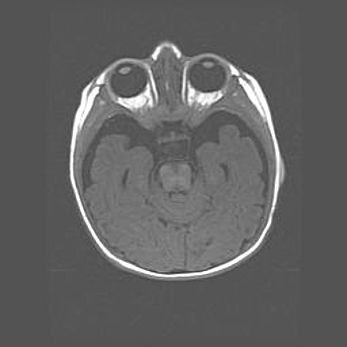

Наружная гидроцефалия с возможной атрофией височных областей.

Возраст: 28 дней

Вес: 3670 г

Пол: мужской

Окружность головы: 38 см

Срок гестации: 40 недель

Гидроцефалия головного мозга у новорожденных – это заболевание, которое характеризуется скоплением избыточного количества спинномозговой жидкости в желудочковой системе головного мозга в результате затруднения её перемещения от места выработки к месту поглощения в кровеносную систему или вследствие нарушения абсорбции. При открытой наружной форме гидроцефалии у новорожденных расширяются и переполняются субарахноидные пространства.

При нормотензивных  формах,  которые,  как  правило,  являются  следствием  перенесенных ишемических  повреждений  паренхимы  мозга,  возможно  сочетание микроцефалии  с нормотензивной гидроцефалией. В основе данных изменений лежит атрофия больших полушарий с преимущественной  локализацией  в  лобно-височных  областях.